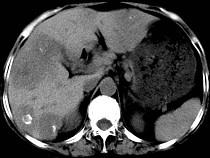

问题 女,55岁,腹胀,肛门闭气,消瘦乏力,肝区疼痛,CT检查如图,最可能的诊断为 ( )

选项 A.多发性肝脓肿 B.肝癌肝内转移 C.肝淋巴管瘤 D.肝脏囊腺瘤 E.结肠癌肝转移

答案 E